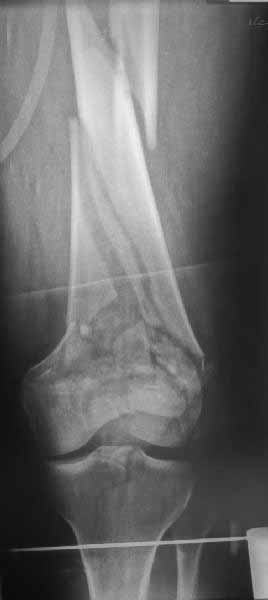

В приложении пример недавней операции, C3, открытая репозиция, фиксация мыщелков спицами и винтами, ретроградный синтез большеберцовым гвоздем 10,5 мм диаметром, винты 5 мм.

Позволю себе напомнить коллегам ещё раз, что являюсь сторонником антеградного остеосинтеза при переломах дистального эпиметафиза бедренной кости. Такая приверженность основана не на преимуществах внесуставного введения стержня или большем проценте положительных результатов. Она основана на возможности обеспечить блокирование на минимальном расстоянии от суставной поверхности в нескомпрометированной кости и, таким образом стабилизировать максимально низкие переломы. В приведенном Вами случае самый дистальный из блокирующих винтов проведен на расстоянии более 2 см от конца стержня. Из-за того, что к стержню присоединяется кондуктор, на стержне теряется 1-1,5 см его длины, где можно было разместить отверстия для блокирования. И что более важно, вместе с потерянной для этой цели длиной стержня утрачивается для размещения блокировочных винтов, пожалуй, самая ценная часть дистального эпиметафиза бедренной кости. Проблемы дистального блокирования в разных плоскостях, локализации точки ввода стержня при антеградном остеосинтезе – это всё решаемые технические проблемы. Но антеградный остеосинтез низких дистальных переломов бедра при адекватном блокировании в нескомпрометированной кости обеспечивает решение стратегической задачи – стабильный остеосинтез и возможность нагрузки.

На этом большеберцовом стержне центр ближайшего к кондуктору отверстия в 14 мм от конца. И пример был про то, что пластина тут, скорее всего, была бы не худшим выбором.